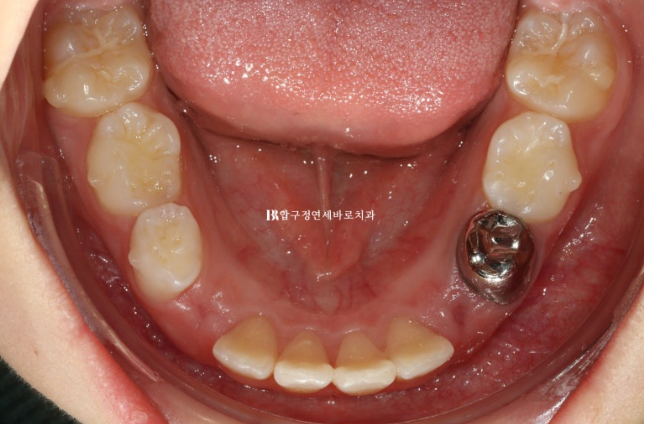

22.11.23

병원에 처음 온 날 모습입니다.

문제점을 나열해보자면

과개교합 (앞니가 깊게 물림)

덧니 (삐뚤빼뚤)

후속 영구치가 나올 공간 부족

그리고 아이의 개인적인 문제점은 당장 한달뒤에 외국에 나가 6개월 후 귀국

이런상황들에 맞춰 치료계획을 만들었습니다.